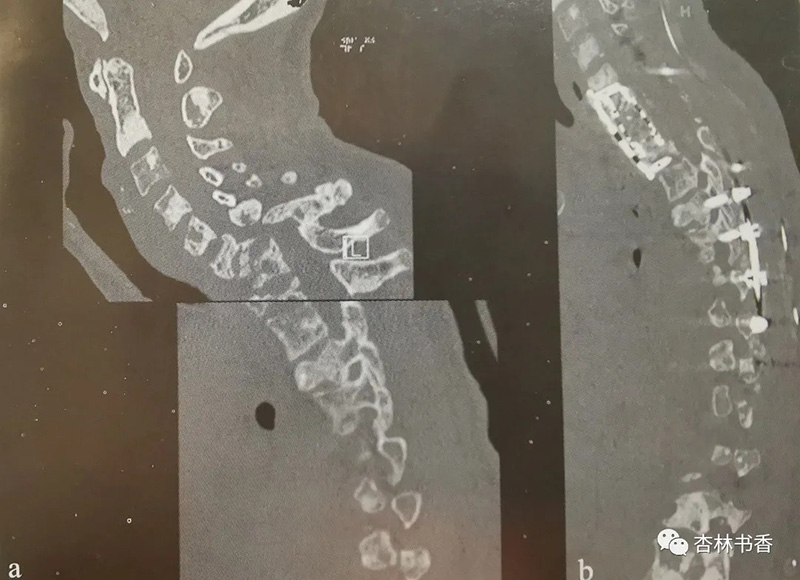

一位39岁乳腺癌患者,虽经化疗,仍出现了广泛骨和脊柱转移。溶骨性转移导致C6和C7扁平椎,椎体高度完全丢失。患者出现了截瘫,在接受放疗和支具固定后,恢复了行走的能力。为她提供的手术方案是分期手术,而术前先行351b(约15.89kg)的牵引来逐步矫正其畸形。第一期手术包括左侧颈前入路和中央胸骨切除,达至左侧颈胸关节。然后通过肺动脉上方和无名静脉下方的“主动脉腔静脉窗”进行前方椎体次全切除。用高速钻石钻头去除C6~T1椎体。此外,还要行C6~T1神经根减压松解,以及C5~T2的钛网植入和接骨板固定。4天后完成第二期手术,行C5~T1双侧全椎板切除术和C2~T8后方固定。治疗过程中患者出现面部水肿、双侧胸腔渗出和肺炎。患者转至康复中心继续治疗,术后存活3年半。

注:颈胸交界处。a.一位乳腺癌颈胸交界转移患者的术前颈胸CT扫描组合图,显示C6-C7扁平椎合并局部后凸畸形和4度前滑脱。术中用高速钻石电钻去除C6-T1椎体。b.在C5-T2前方置入钛网(cage)和支撑接骨板。4天后,通过C5~T1双侧椎板切除和C2~T8后方固定,完成第二期手术。